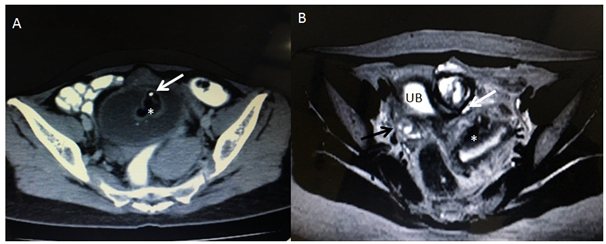

There was a pelvic ultrasound done by a local sonologist which reported a mass in the urinary bladder with normally visualized both ovaries & uterus. The scan was repeated and revealed an intra vesicular echogenic mass (Figure 2) with normal right ovary and uterus. However; left ovary was not visualized. Due to non visualization of the Ovary, the patient was advised to get a pelvic MRI, which revealed a mixed intensity lobulated well defined mass along the dome of the Urinary bladder with both intra & supra vesicular components (Figure 3). There were internal T1 hyper intense areas showing low intensity on fat suppression and a focus of signal void; suggesting internal fat and calcific intensities, respectively. Few small cyst like foci (follicles) could be visualized in the supra vesicular component of the mass with non visualized separate left ovary. Right ovary and Uterus were normal. Diagnosis of Left Ovarian dermoid cyst with cysto-vesical fistula was made. In view of academic interest and for diagnostic correlation, pelvic CT scan was acquired; under complete patient satisfaction and informed consent (Figure 4).

Figure 2 Pelvic trans abdominal ultrasound image showing echogenic mass in the urinary bladder lumen with normal uterus.

Figure 4 (A) Pelvic CT scan axial image showing intra vesical lesion of fat attenuation (asterisk) and focal calcification.(white arrow).

(B) T2 W Axial MRI pelvis image at the level of dome of the Urinary bladder (UB) is showing left ovarian tissue contained dermoid and peripheral normal follicles (white arrows). Right ovary (black arrow) and Uterus (astersik) are normally visualized.